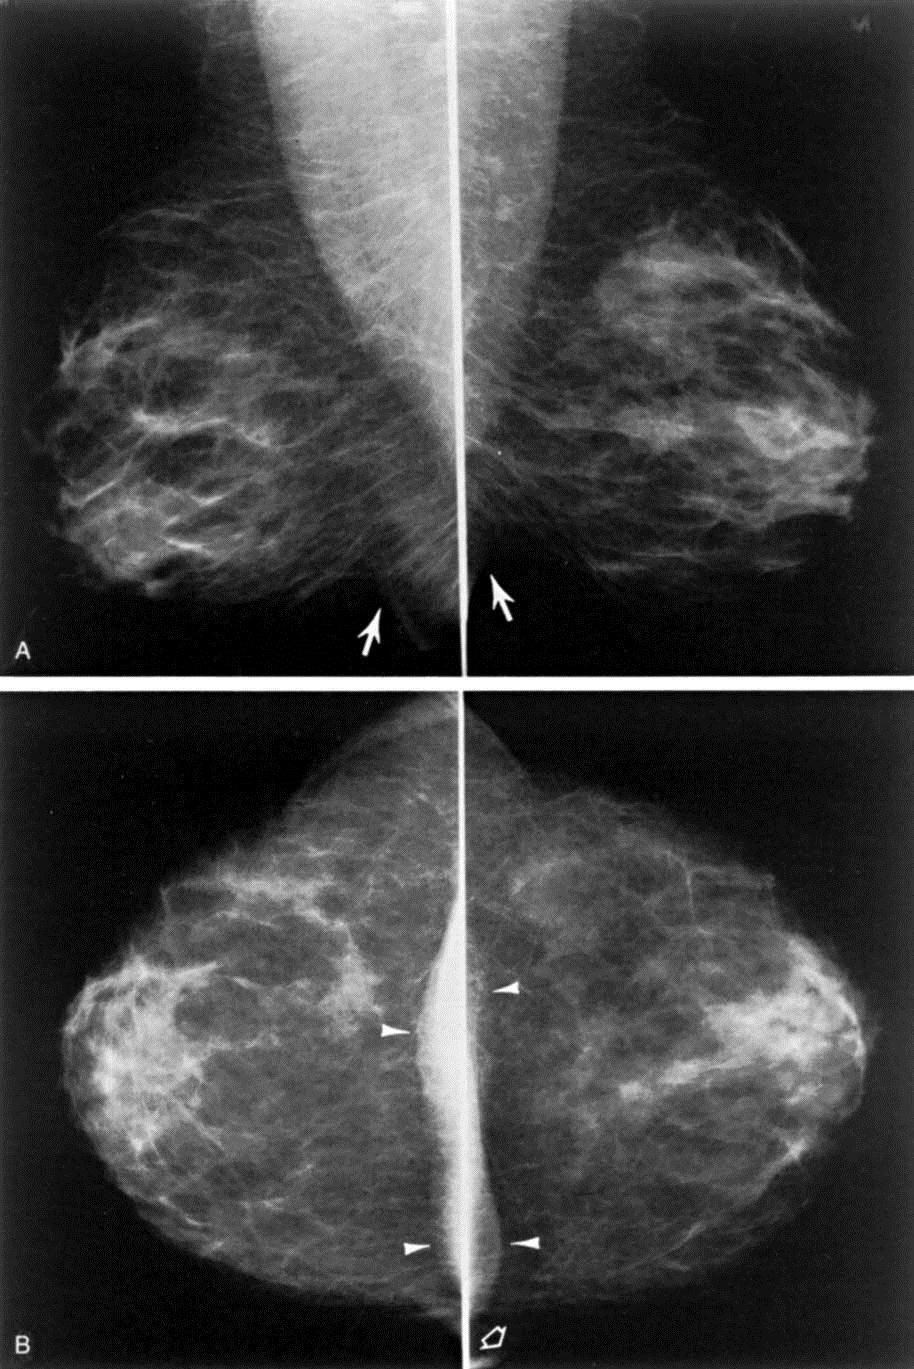

בתמונה: שינוי בתמונת הממוגרפיה הנ"ל, לאחר שהאשה קבלה טיפול הורמונלי במשך מספר חודשים